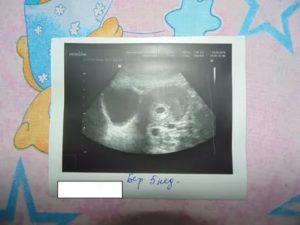

Первый раз УЗИ делается с целью подтверждения беременности. Как правило, его назначают сразу же после того, как у женщины возникла задержка – на 4-5 неделе гестации.

Последующие плановые УЗИ осуществляются на 11-12, 21-22, 32-33 и 38-39 неделе беременности.

Но если после 12 недели проводится ультразвуковое наружное исследование, то до этого срока делается вагинальное УЗИ.

После того как женщина забеременела, необходимо удостовериться, что плод формируется и развивается правильно, у него нет аномалий, а если есть небольшие отклонения, то вовремя их скорректировать при помощи лекарств.

Для этого делают ультразвуковое исследование. После УЗИ при беременности бывают коричневые выделения. Нормой считаются скудная мазня, небольшой тонус, слабые боли внизу живота.

Поводом для обращения к врачу являются обильные кровянистые выделения, длительный тянущий дискомфорт в пояснице и внизу живота.